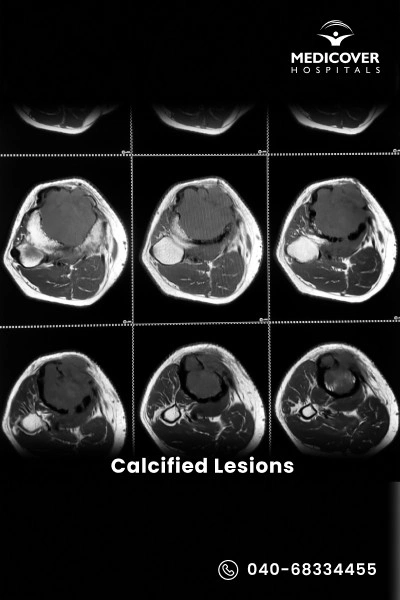

What Is a Calcified Lesion?

Calcified lesions, also known as calcifications, are abnormal calcium deposits that build up in tissues, blood vessels, organs, or even the brain. They are often detected through imaging tests like X-rays, CT scans, or MRIs. While some are harmless, others may result from chronic inflammation, injury, metabolic disorders, or circulatory problems, and can lead to pain, stiffness, or organ dysfunction depending on their size and location.